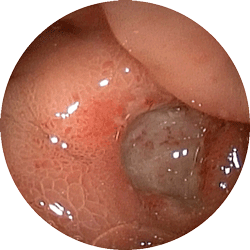

十二指腸潰瘍1

十二指腸潰瘍

お腹が張る,つかえる感じで

来院

内服薬にて1ヶ月で治癒